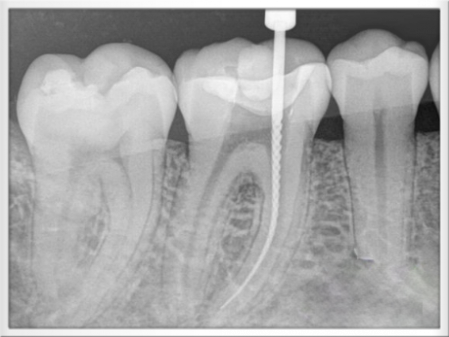

El tratamiento es conveniente cuando por algún motivo los conductos del diente son contaminados por bacterias, llegando a dañar el nervio, los conductos radiculares, la raíz o el hueso maxilar dónde se alberga el diente. Las causada principalmente para esta contaminación son por:

- Caries

- Dientes fracturados

- Lesiones periodontales

- Tallado protésico para la colocación posterior de coronas o puentes.

-Traumatismos dentarios